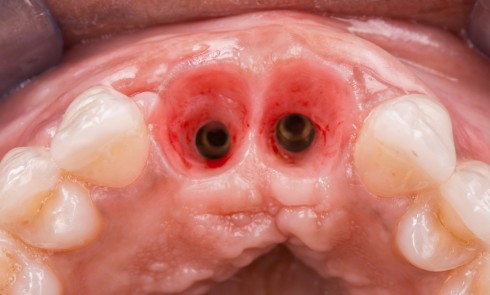

L’examen clinique révèle une différence d’alignement et un tissu gingival péri-implantaire peu épais sur cette couronne implanto-portée.

L’implant a été posé alors que la patiente était âgée de 17 ans (le 13 août 2004), à la suite d’un traumatisme entraînant la perte de cette dent (fig. 2a à d), puis la couronne a été posée 5 mois plus tard (le 7 janvier 2005).

Nous proposons de retirer la couronne et le pilier implantaire, d’effectuer une greffe de tissu conjonctif enfouie afin d’améliorer le volume du tissu kératinisé péri-implantaire [5] et de procéder à la pose d’une couronne provisoire transvissée (fig. 3a à h).